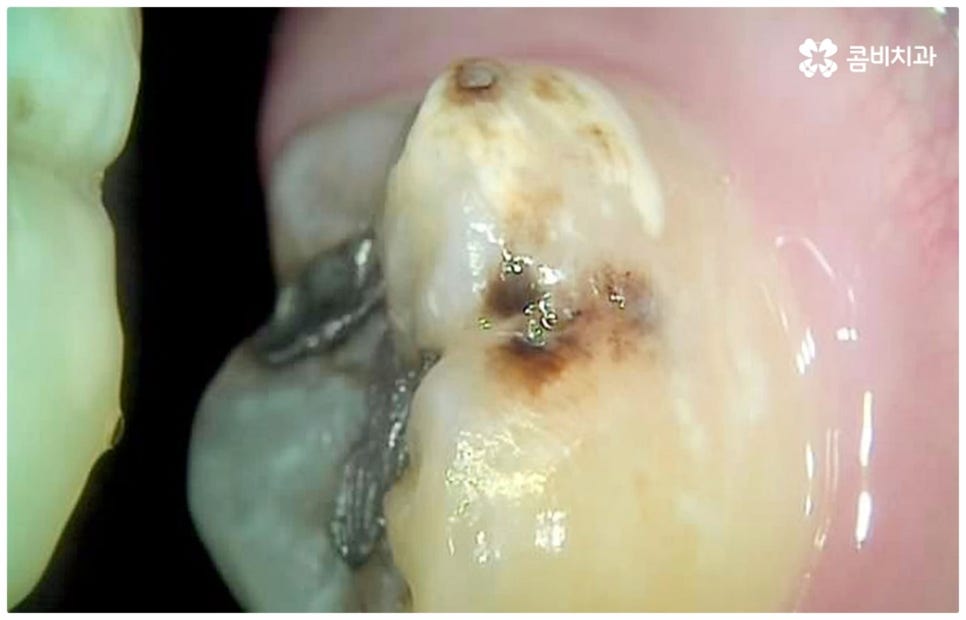

만약 충치가 어느 정도 진행되어 상아질까지 손상되면 비로소 시리거나 쑤시는 듯한 통증이 생기며 이 때 치과에 내원하시면 정도에 따라 감염 부위를 제거하고 어금니충치치료 방법 중 인레이 또는 온레이를 통해 수복하게 되는데, 이 시기를 지나 병증이 더욱 심해지면 내부 치수조직을 제거하는 신경치료를 진행하게 될 거예요.

치아의 가장 겉부분인 법랑질은 인체에서 제일 단단하지만 안쪽으로 들어가면 비교적 무른 상아질과 신경, 혈관이 많이 모여 있는 연조직인 치수가 자리잡고 있으며 만약 이러한 치수가 존재하는 근관 내부가 구강 질환으로 인해 세균에 감염되거나 외부 충격으로 인해 치신경이 노출되어 손상되었을 때에는 근관치료라고도 불리는 신경치료를 통해 이를 치료해 주실 필요가 있습니다. 즉, 세균이나 염증 등으로 돌이킬 수 없을 정도의 손상을 입은 신경을 제거하고 근관을 깨끗하게 소독한 후 빈 공간에 생체친화 충전재를 채워넣어 밀봉한 다음 주변 치아와 높이와 각도 등을 맞춰서 크라운으로 수복을 해주어 남아 있는 자연 치아를 발치하지 않고 보다 오랜 기간 동안 사용할 수 있도록 하는 보존 치료의 일종이 바로 신경치료 및 후속 처치인 크라운 치료인 거예요.

평상시에 꼬박꼬박 검진이나 스케일링 치료를 받으시는 분들이 점차 많아지고 있는 반면 시간이 없어서 또는 막연한 두려움으로 인해서 더 이상 통증을 참을 수 없을 지경에 이르러서야 치과에 가시는 분들도 있을 거예요. 그런 경우 대부분 내원을 하신 시점에 이미 치아 내부 손상이 상당하고 살릴 수 있는 자연 치아가 굉장히 적을 수 있어요. 그러므로 이 중 몇몇 케이스는 굉장히 복잡한 고난도의 신경치료 대상이 될 수 밖에 없으며 혹시라도 미세한 부근관의 감염을 놓치게 되면 재신경치료를 해야 할 수도 있습니다. 이럴 때는 신경치료를 받은 후에 얼마 지나지 않아 해당 치아를 쓸 수 없게 되는 결과가 나올 수도 있는데요. 그러면 어금니충치치료 를 하여 괜히 힘만 두 번 들이고 고생을 하는 것 보다는 바로 임플란트 단계로 가는 것이 낫지 않느냐고 문의를 주시는 분들도 있어요.